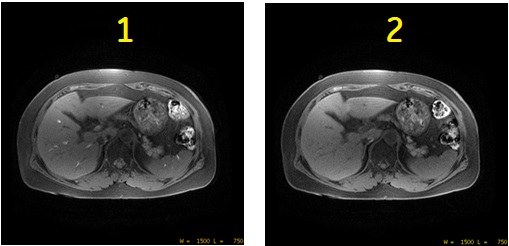

In-flow artifact

T1-weighted images normally have a dark vessel signal due to saturation effects. This vessel signal can be clinically confusing in regions that have a short T1. The vessel signal becomes bright due to an in-flow effect around the edge slices or in 2D multiple acquisitions with an interleaved slice order.

| Number | Description |

|---|---|

| 1 | 2D FSPGR acquired with In-flow signal reduction User CV set to OFF (=0). |

| 2 | 2D FSPGR acquired with In-flow signal reduction User CV set to ON (=1). |